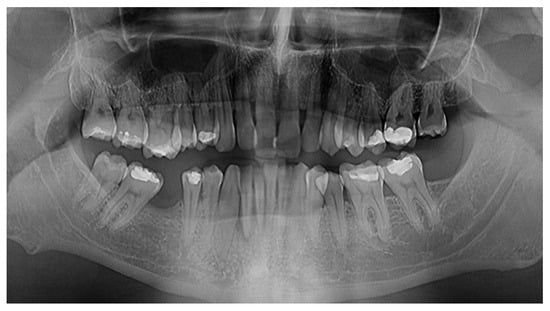

2.1. Patient Presentation

2.2. Initial Consultation